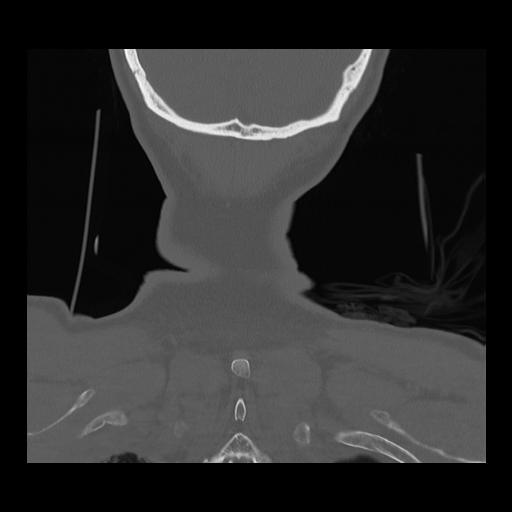

16 HUESO,,Coronal,2.000,HUESO,Coronal,